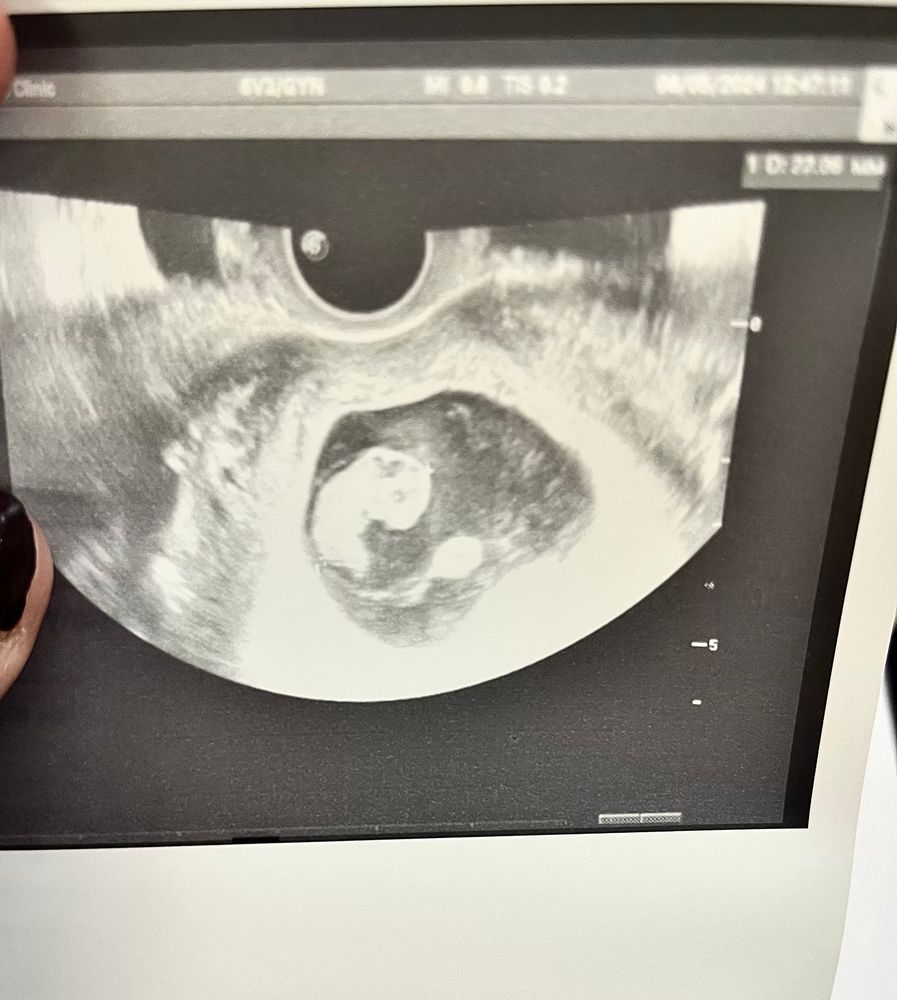

Дарина в Зачатие год Покидайте фото узи в 9 недель 🙏🏻 УЗИ Девочки у кого остались или есть фоточки покидайте пожалуйста! Хочу сходить в 9 неделек на узи, с монитором, хочется узнать как что там примерно видно будет Посмотрите еще 20 записей на эту тему Лучший ответ Елена 9н 2д двойня 02.11.2024 Ответить Отменить Ответить Таня Орозова 01.11.2024 Ответить Екатерина 01.11.2024 Ответить Екатерина Екатерина, чуть больше, 9,5 01.11.2024 Ответить Евгения 9+3 недели 01.11.2024 Ответить ЛисАлис 01.11.2024 Ответить Екатерина 01.11.2024 Ответить Екатерина Екатерина, 9 недель ровно, первое УЗИ 01.11.2024 Ответить Екатерина Екатерина, ножки попка к верху 😄 01.11.2024 Ответить Дарья 01.11.2024 Ответить Евгения Дарья , а вам делали трансвагинально или абдоминально? 01.11.2024 Ответить Дарья Евгения, трансвагинально . А вот 10 недель узи) 01.11.2024 Ответить Евгения Дарья , ух ты) а мне абдоминально делали😁 как в этот раз будут не знаю, пойду в другое место 01.11.2024 Ответить Евгения 01.11.2024 Ответить Мира В интернете нашла)) 01.11.2024 Ответить Девочки подскажите !! Пост нытья Чаты Беременных Выберите чат: Январята-2026 Февралята-2026 Мартята-2026 Апрелята-2026 Майчата-2026 Июнята-2026 Июлята-2026 Августята-2026